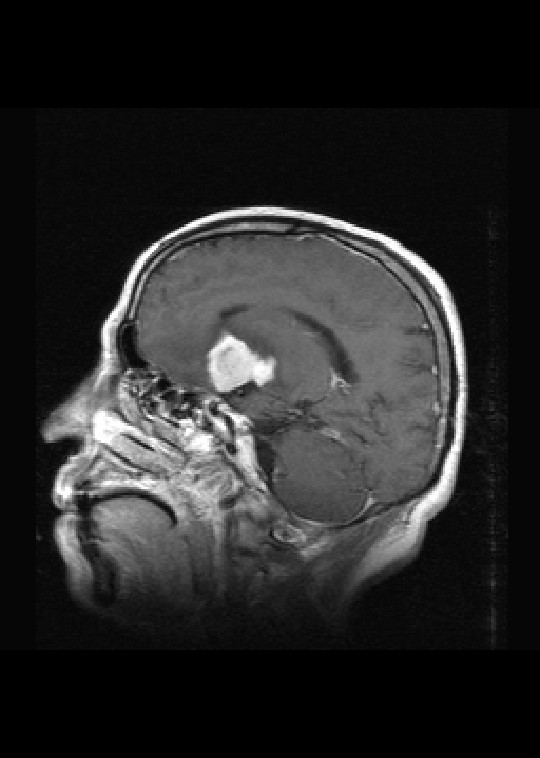

标题: MRI2527:脑部肿瘤,(病理结果:淋巴瘤)

(左额颞叶)非霍奇金淋巴瘤,b细胞性,弥漫性大b细胞型。免疫组化结果:cd45(lca) +,vimentin +,ck(ae1/ae3) -,ema -,cd3 -,cd20 +++,cd30 -,plap -,cd79a +,gfap -,alk -,s-100 -。

左侧基底节区病灶t1wi呈不均匀稍低信号,t2wi呈稍高信号,周围伴有水肿。增强扫描呈均匀团块样或者抱拳样明显强化,相邻的柔脑膜亦见线样强化。首先考虑淋巴瘤。可惜没有ct平扫,如果ct平扫病灶呈高密度,那么更支持pcnsl的诊断。

病理结果:(左额颞叶)非霍奇金淋巴瘤,b细胞性,弥漫性大b细胞型。免疫组化结果:cd45(lca) +,vimentin +,ck(ae1/ae3) -,ema -,cd3 -,cd20 +++,cd30 -,plap -,cd79a +,gfap -,alk -,s-100 -。

左侧基底节区病灶t1wi呈不均匀稍低信号,t2wi呈稍高信号,周围伴有水肿。增强扫描呈均匀团块样或者抱拳样明显强化,首先考虑淋巴瘤。